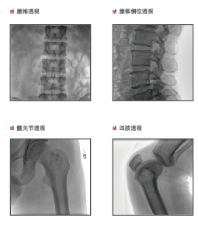

普愛醫療是專業從事平板小C生產、研發、售后為一體的廠家,目前我們應用在國內很多醫院的一款PLX118F平板C形臂,它是一臺集光、機、圖像處理技術為一體的帶數字減影血管造影功能(DSA)的可移動式X光機,該設備占地面積小、圖像清晰、定位精準、輻射劑量小,是疼痛科醫生的可靠眼睛,對于疼痛介入手術的精準化治療、滿足患者對慢性疼痛治療需求提供了有利條件。